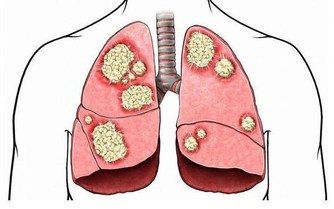

糖尿病、高血壓、癌症、神經衰弱、失眠、生育能力下降、女性閉經或月經不調、乾眼症等眼科疾病、皮膚暗黃長痘等都會不請自來。

我的閨蜜,熬夜四年,是護士,最後得癌症去世了。